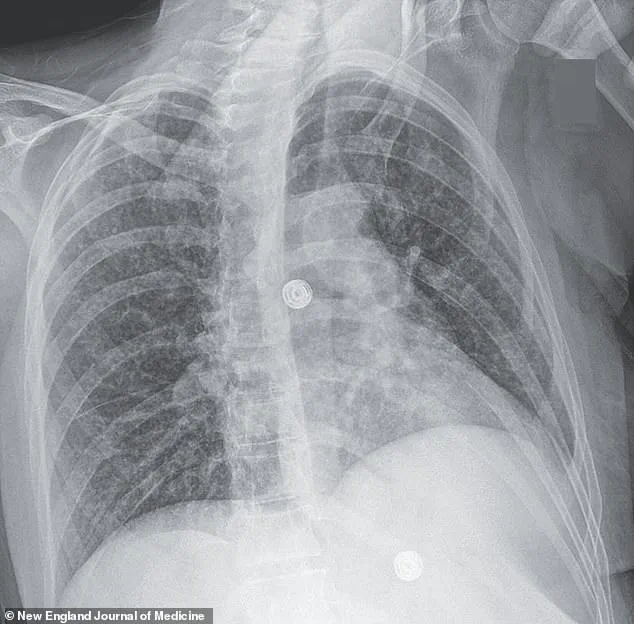

X-ray scans revealed an alarming finding: multiple small nodules scattered across her lungs, a hallmark sign of bacterial infection.

TB is a disease of the lungs, but its reach extends far beyond the respiratory system.

The bacteria, *Mycobacterium tuberculosis*, spreads through airborne droplets when an infected person coughs, sneezes, or speaks.

In its early stages, the disease may manifest with symptoms as subtle as a persistent cough, chest pain, or unexplained weight loss.

If left untreated, it can progress to severe respiratory failure, with the infection spreading to other organs, including the brain, liver, and lymph nodes.

A recent case study highlights this grim reality: a woman’s scans revealed nodules in her lungs, liver, pancreas, and brain, with an enlarged lymph node in her chest.